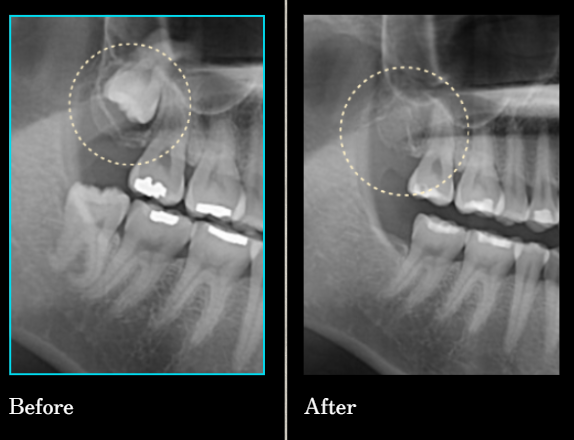

수많은 환자의 경험과 신뢰로 증명된

연세원치과 사랑니 발치입니다.

*위 케이스는 본원에서 진행 받으신 분의 동의 후 동일한 촬영 조건에서 촬영한 사진을 사용하였습니다.